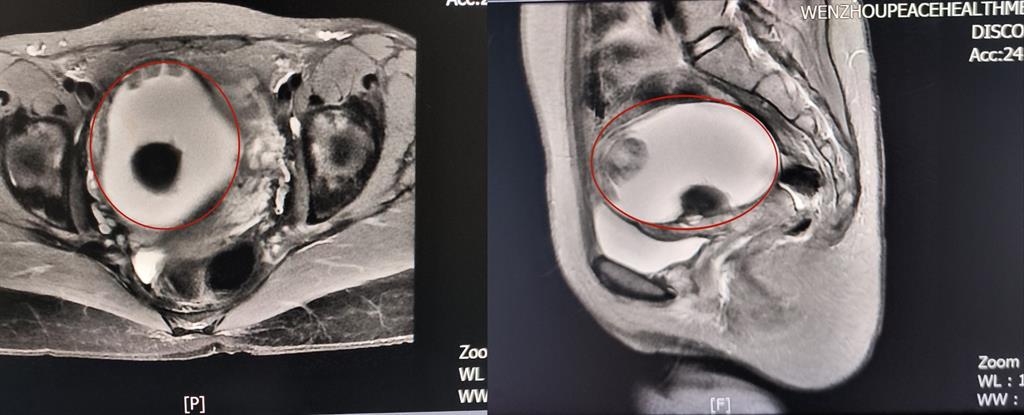

前不久,溫州某高校外籍教師A女士來到和平國際醫(yī)院體檢與健康管理中心進(jìn)行深度體檢。B超提示“子宮右側(cè)附件區(qū)囊性塊,大小約82*79*88mm”和平國際醫(yī)院婦科主任醫(yī)師方軼萍發(fā)現(xiàn),A女士還有三項(xiàng)腫瘤標(biāo)志物數(shù)據(jù)超標(biāo)(甚至高出正常值兩倍)。

卵巢腫瘤?為進(jìn)一步明確診斷,A女士在方主任建議下做了增強(qiáng)磁共振,影像結(jié)果提示:盆腔右側(cè)團(tuán)塊狀占位伴多發(fā)成熟脂肪成分大小約89*100*71mm,考慮畸胎瘤可能性大。謎團(tuán)逐漸解開,原來那個(gè)“怪胎”可能是畸胎瘤在作祟。